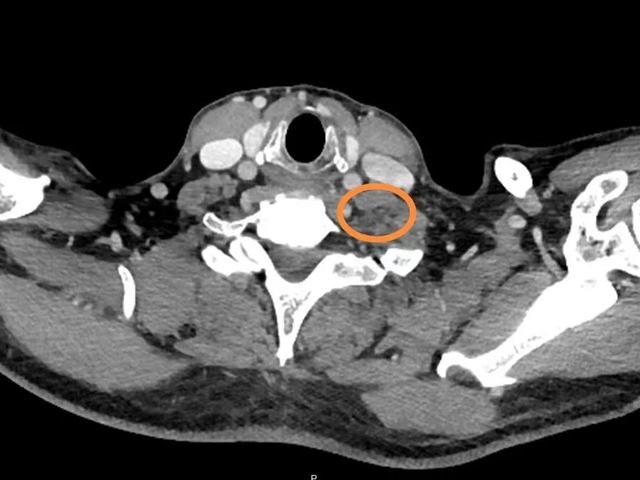

2周期化疗后,复查CT左侧颈根部软组织肿块,最大截面大小约为2.4cm*2.2cm。与上次检查结果比较,颈、胸、腹部淋巴结均有缩小,左侧胸腔积液减少,双肺结节有明显缩小,部分已被吸收。

治疗后